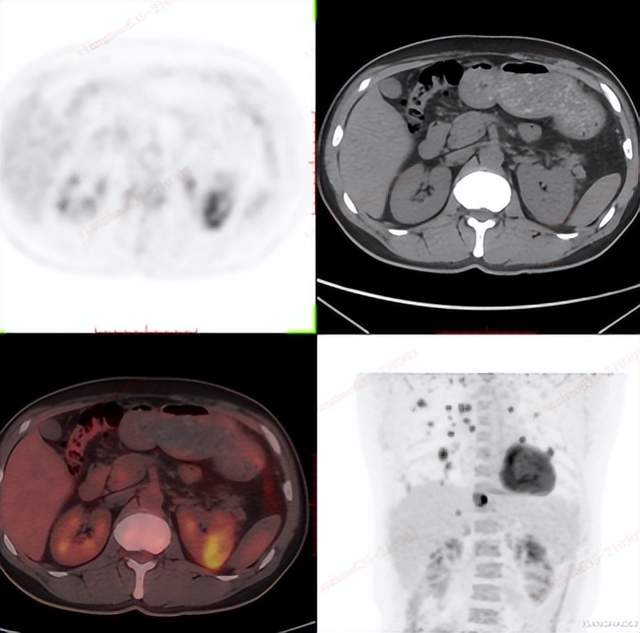

PET/CT检查卵巢癌

女性,60岁

相关病史:宫颈高级别鳞状上皮内病变(HSIL)锥切术后4月;否认结核及其他慢性病史。无其他临床症状。已绝经,无外伤史。2021-3-21日,患者因检查发现CA125渐进升高(250U/mL)后,在平安健康(检测)中心接受PET/CT检查。

PET/CT影像学表现

结论: 盆腔双附件区结节灶(左侧著)、右侧膈前上、肝脏包膜及腹盆腔多发结节灶、腹膜后多发淋巴结FDG代谢增高,考虑:卵巢癌(源于左侧卵巢可能性大)并上述部位多发转移瘤

PET/CT结论与病理结果对比

PET/CT结论:

考虑:卵巢癌(源于左侧卵巢可能性大)

手术病理结果:

卵巢癌

对比结论:

PET-CT实现肿瘤的精准定位及确诊。